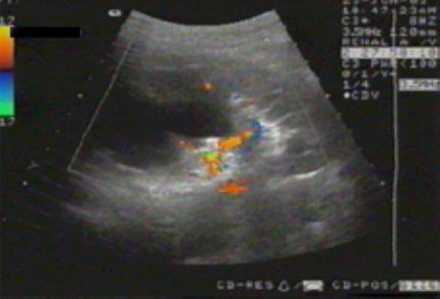

Эходоплерография сосудов почек.

Эходопплерограмма. Снижение интенсивности кровотока в области истонченной паренхимы верхнего и среднего сегментов почки.

Исследование актуально для оценки гемодинамических отклонений. Патология приводит к трансформации органа и растяжению артериальных и венозных сосудов. По их размерам можно судить о стадии и корректно выбирать лечение.